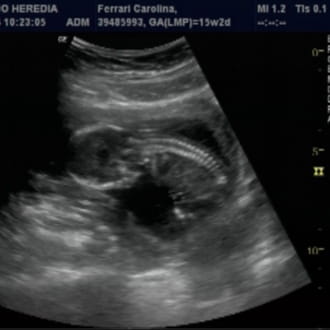

Te cuento, no tube tiempo para escribir . Pero leí tu comentario cuando lo hiciste. Fui a mi ginecologa .. Me hizo una ecografía transvaginal y me dio que estába embarazada de 6 semanas, se veía perfecto como latía su corazoncito a dos mil . Estaba digo porque hoy estoy de tres meses.. Muchas Gracias por tu comentario. Besos!